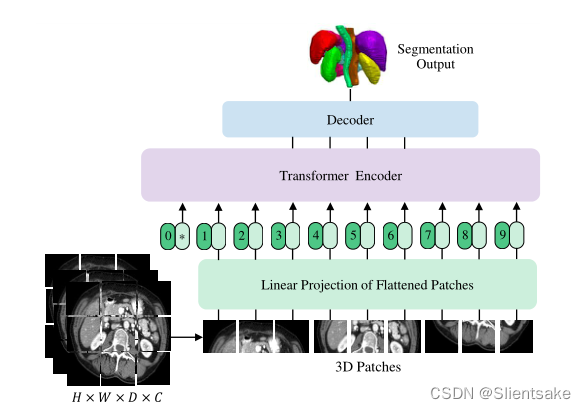

损失函数:

损失函数是soft-dice损失和交叉熵损失的组合,它可以按体素方式计算:

其中I为体素的数量;J为类数;Yi,j Gi,j分别表示j类在体素i上的概率输出和one-hot编码ground truth。